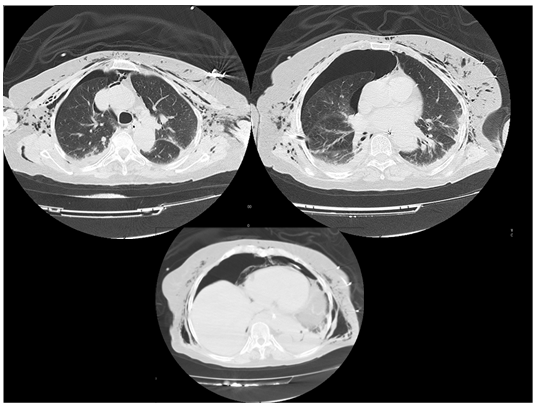

A 77-year-old female patient with an ASA physical status II was proposed for elective laparoscopic fundoplication due to a huge esophageal hiatal hernia. The preoperative exams were within the normal range. The patient was medicated with metoclopramide 10mg IV and esomeprazole 40mg IV on the morning of surgery. In the operating room the electrocardiogram, blood pressure, heart rate, urine output and oxygen saturation were monitored. After pre-oxygenation with 100% oxygen, anesthesia was induced with fentanyl 3µg/kg IV and propofol 2mg/kg IV. Endotracheal intubation was performed after administration of rocuronium 0.6 mg / kg IV, mechanical ventilation initiated and a nasogastric tube placed. Anesthesia was maintained with sevoflurane for a minimum alveolar concentration of 1, and fentanyl and rocuronium were administered, as needed, in bolus. Surgery was initiated and insufflation of the peritoneum took place without incidents. At 100 minutes of surgery, a progressive increase in airway pressure and of expired CO2 was detected (Table 1). Pulmonary auscultation was normal but the ventilatory changes were promptly reported to the surgeons who immediately reduced the pressure of the pneumoperitoneum. Adjustments in ventilation parameters were also undertaken. These measures were, however, not effective and, at 135 minutes of surgery, a severe increase in airway pressure (40 cmH2O) and end tidal CO2 (75mmHg) was noted, with a sudden onset of marked subcutaneous emphysema of the neck and chest. Auscultation did not revealed any altered breath sounds, with symmetrical vesicular murmur but a positive Hamman´s sign was present. Concomitantly, the patient showed marked bradycardia and hypotension that improved with 0.5mg of IV atropine,5 mg of IV ephedrine and infusion of 500 mL of colloid solution. The peripheral oxygen saturation, with 60% of inspired oxygen, never showed values below 97% (Table 1). At this moment, the pneumoperitoneum was immediately stopped and two chest tubes were placed, one in each hemithorax. The subcutaneous emphysema showed a frank decrease and the end tidal CO2, airway pressure, blood pressure and heart rate normalized. Since the surgery was in its final phase, the pneumoperitoneum was resumed, and the intervention ended 15 minutes later. Because of the suspicion of capnomediastinum, we decided not to extubate the patient. Patient was taken to perform a tomography of the chest, deeply sedated and under continuous monitoring. An extensive right capnothorax and slight left capnothorax was revealed, as well as residual capnomediastinum and subcutaneous emphysema (Figure 1). The patient was then transferred to the polyvalent intensive care unit for close monitoring. At 28 hours of admission the patient was extubated and chest drains were removed. The following day the patient was transferred to the general surgery ward and stayed there for seven days due to delay in resumption of normal bowel movements. The patient was then discharged from the hospital without pulmonary complaints and with normal chest radiography.

Figure 1 Thoracic computerized tomography showing capnothorax, capnomediastinum and subcutaneous emphysema.